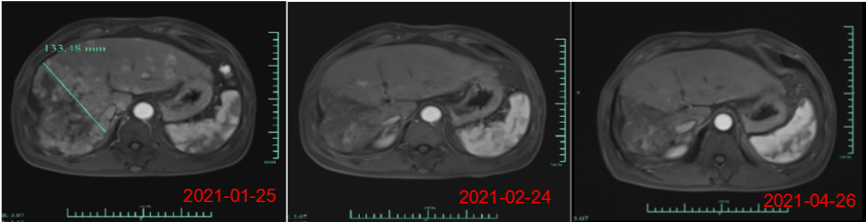

楊煥鳳表示,近期公司在美國臨床腫瘤學(xué)會 (ASCO)發(fā)表了核心產(chǎn)品Ori-CAR-001在治療難治復(fù)發(fā)型肝細(xì)胞癌的探索性臨床研究數(shù)據(jù),截至三月份,在9例可評估數(shù)據(jù)中,有4例獲得PR(部分緩解),截止到目前,受試者007的緩解周期已超過是9個月,還有一例受試者012的PR緩解周期已達(dá)5個月,其腫瘤縮減的幅度接近93%。

此外,最近的一個新的爬坡劑量的首個患者也獲得了PR(自ASCO數(shù)據(jù)發(fā)布后,又新增了一位部分緩解的病人)。目前,這些病患目前仍在持續(xù)隨訪中?!霸谕砥趯嶓w腫瘤治療中,這個緩解時間還是相當(dāng)長的,腫瘤減小的幅度也是非常驚人的,這個結(jié)果令團隊很受鼓舞,我們期待在進一步的產(chǎn)品開發(fā)和臨床研究過程中,獲得更好的數(shù)據(jù)。